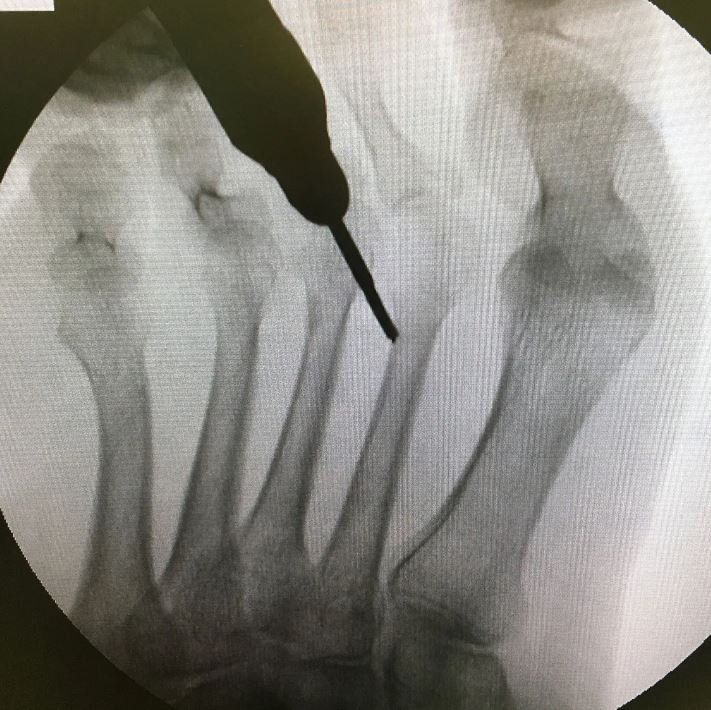

La chirurgia del piede mini-invasiva si riferisce a un tipo di intervento chirurgico eseguito con un'incisione molto piccola che richiede una sutura minima. Attraverso queste incisioni estremamente piccole, si inseriscono strumenti appositamente progettati per eseguire l'operazione. La piccola esposizione cutanea e la bassa invasività a livello dei tessuti locali, consentono un recupero più rapido e gestibile dopo l'intervento. La chirurgia mini-invasiva è stata introdotta per la prima volta dal Dr. Morton Polokoff nel 1945, sviluppando queste tecniche come un sistema di chirurgia sub dermica utilizzando strumenti molto piccoli. Nei decenni successivi, ulteriori progressi chirurgici hanno portato alle procedure all'avanguardia che eseguiamo oggi, rendendo la chirurgia mini-invasiva molto più sicura e confortevole per i pazienti.

Con un intervento chirurgico mini-invasivo, si verificano meno lesioni ai tessuti molli. Rispetto alla chirurgia tradizionale aperta in cui vengono effettuate lunghe incisioni che possono creare più traumi ai tessuti molli, la chirurgia mini-invasiva utilizza incisioni molto più piccole che disturbano meno tessuti e che portano a tempi di recupero più rapidi.

Poiché esiste una piccola incisione, i tempi chirurgici per le procedure di chirurgia del piede minimamente invasive sono spesso più brevi rispetto agli interventi chirurgici aperti tradizionali.